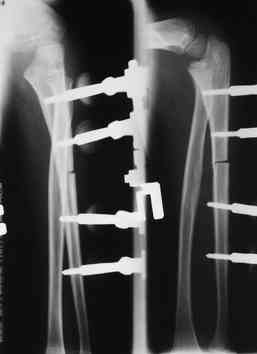

Иллюстрация к лечению застарелого повреждения Монтеджиа

Пациентка клиники детской травматологии ЦИТО

Многоуважаемые коллеги, всем большое спасибо!!! Да, здесь было повреждение Монтеджиа, когда нарисовал скиаграмму все стало понятно. Мне очень понравились рекомендации Константина Требухина, только немножко видоизменил; я считал так, если деформацию исправить то локт/кость должна удлиниться, и во вторых, если на аппарате низвести лучевую кость, то может наступить позиционное несоответствие в дистальном радиоульнарном сочленении. 28.02.08г операция - шарнирная остеотомия локтевой кости на уровне деформации, далее вскрыт плечелучевой сустав, удалены рубцовые тканы, после исправления варусной деформации и создания физиологического изгиба локтевой кости головка луча легко вправился, из части рубцовой ткани сделана пластика кольцевндной связки, трансартикулярная фиксация спицей, локтевая кость двумя спицами.

оперировали подобный случай около 6 мес назад. Отличие только в одном- давность травмы была до 2х лет. Использовали методику описанную в "Pediatric fractures and dislocations" Lutz von Laer, M.D.

Артротомия, иссечение рубцов, остатков кольцевидной связки. На проксимальный отдел локтевой кости стержневой аппарат (рекомендуют

Compact II выпущеный Stryker Howmedica, но за неименеем...), остеотомия проксимального отдела локтевой кости, вправление головки лучевой кости, замыкание аппарата, проверка стабильности головки

лучевой кости в движении, ушивание без пластики кольцевидной связки.

1 подвывих головки лучевой кости в положении супинации - через 2 недели после операции- под ЭОП: аппарат разблокирован, повторное вправление головки, стабилизация аппарата.

2 По снятии аппарата через 2 мес после операции рефрактура в месте остеотомии(на фоне активного ротационного движения)- под контролем ЭОП выполнен

интрамедуллярный остеосинтез TEN. Положение головки луча стабильное.